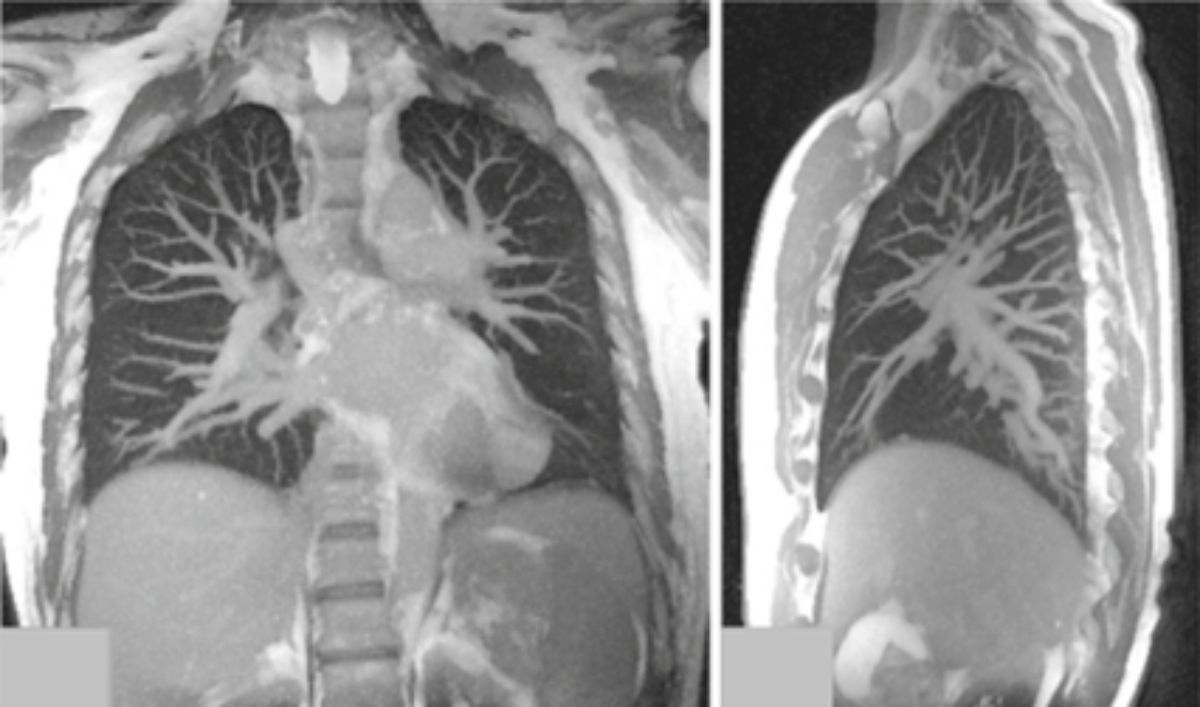

«Unsichtbar»?

«Unsichtbar» – vergleichen wir Bild und Urteil zur Lungenbildgebung mittels Magnetresonanztomografie (MRT/MRI) zeigt sich, was unsere Forschung erreicht hat. Bis vor Kurzem galt, dass die Lunge mittels der MRT nicht dargestellt werden kann. Die Probleme, eindeutige, verwertbare Signale zu erhalten, liegen primär am hohen Luftanteil und der stetigen Bewegung des Organs. Unsere Wissenschaftler*innen der radiologischen Physik forschen dennoch seit Jahren an entsprechenden speziellen Verfahren – mit sichtbarem Erfolg.